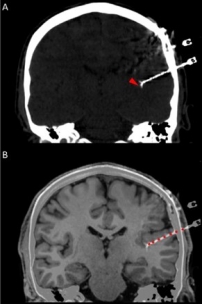

Our research leverages on the rare opportunity of measuring brain activity intracranially in patients affected by pharmaco-resistant epilepsy. In pharmaco-resistant epilepsy patients, neurologists use intracranial electroencephalography (iEEG) to delineate the epileptogenic focus, when non-invasive scalp EEG and other techniques have been insufficient to localize it. iEEG is recorded with intracranial electrodes and it has higher spatial resolution and higher signal-to-noise ratio than scalp EEG.

In addition to the very valuable iEEG recordings from the clinical macroelectrodes, our iEEG recordings also include signals recorded with microelectrodes. The additional microelectrodes have a diameter of about 40 μm (smaller than the hair) and spread out of the tip of the clinical intracranial electrode. They are added solely for research purposes and, because of their small size, they can record the electrophysiological firing activity generated by nearby individual neurons. We analyze this data by using algorithms which classify the different waveforms recorded by a single microwire into action potentials generated by different neurons. We also use population decoding methods to extract the information associated by the neurons (e.g. “concept” neurons which preferably fire in response to specific images of the same individual). To localize the site of the macro- and micro-electrodes with high spatial resolution, we combine post-implantation CT scans with pre-implantation neuroimaging scans from the 7-Tesla MRI, available at the University of Magdeburg.

1. © Grande et al. 2020. The image is a cropped version of the original. Reproduced according to the terms of Creative Commons Attribution License. Grande, Krista M., Sarah K. Z. Ihnen, and Ravindra Arya. 2020. “Electrical Stimulation Mapping of Brain Function: A Comparison of Subdural Electrodes and Stereo-EEG.” Frontiers in Human Neuroscience 14 (December). https://doi.org/10.3389/fnhum.2020.611291.

2. © Greene et al., 2021. Reproduced according to the terms of Creative Commons Attribution License. Greene, Patrick, Adam Li, Jorge González-Martínez, and Sridevi V. Sarma. 2021. “Classification of Stereo-EEG Contacts in White Matter vs. Gray Matter Using Recorded Activity.” Frontiers in Neurology 11 (January). https://doi.org/10.3389/fneur.2020.605696.